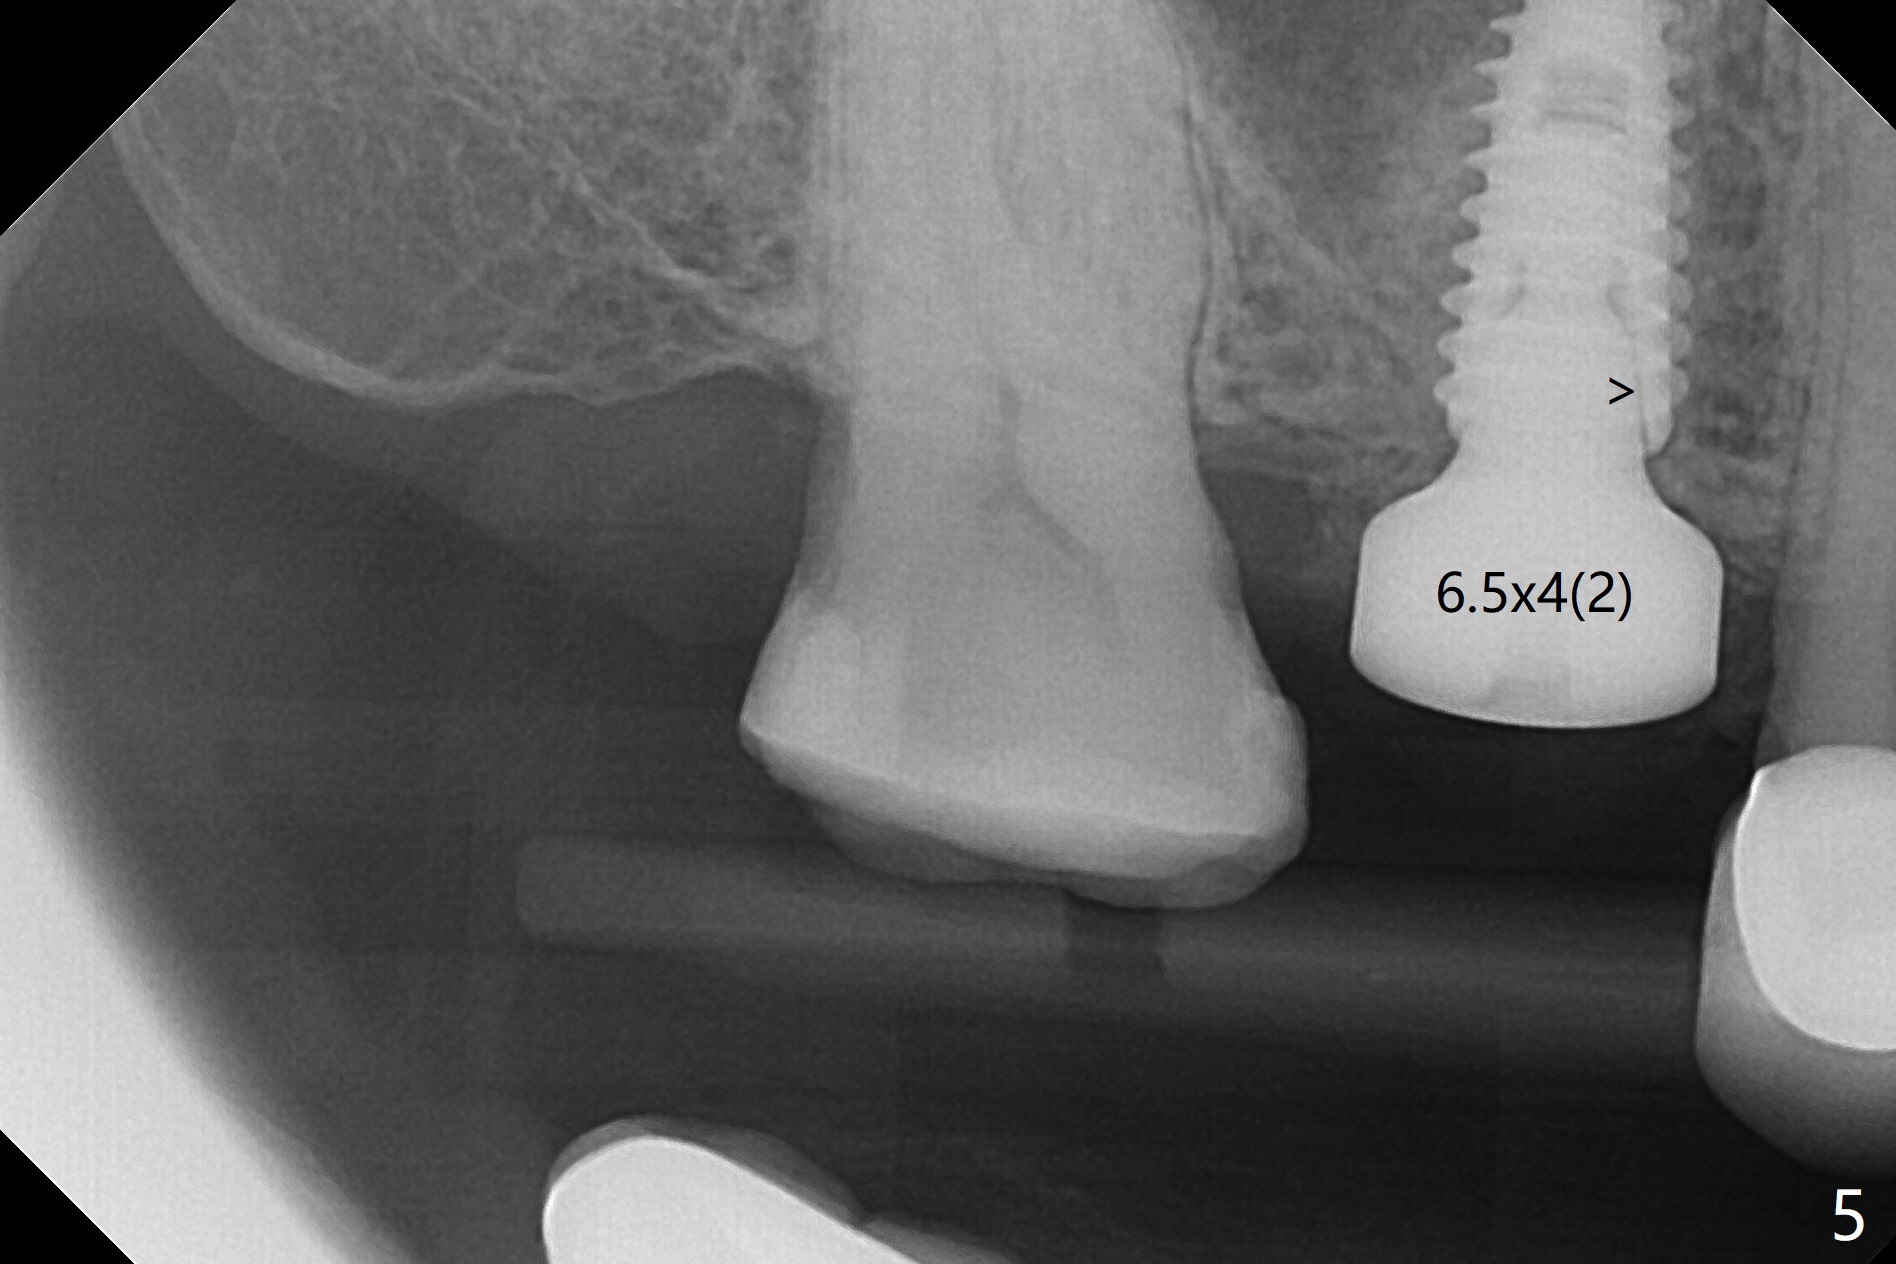

我们将使用粘性骨块做上颌窦内提升。抽血,一个红试管(含促凝剂),离心每分钟1500转,3分钟,提取上清液,与异体骨混合,几秒钟骨粉就开始凝聚(录像)。右上六缺牙区切开,开始用2毫米钻头钻洞,深度4毫米,如何使用2.8,3.6毫米园钻头(对上颌窦膜安全),4-6 毫米深,由于上颌窦底板是斜型,没有突破感。接着想利用粘性骨块和报废植体,把骨块送上去,这时骨块相当硬,必须事先剪成适当大小,然后用报废植体(4x10毫米)慢速推上去(录像2,图一(*骨块))。数次提升后,放置4.5x8.5毫米正式植体(图二),调整植体深度(图三:<),在稍微暴露植体表面放置骨块(图四:*)。其实愈合基台没有就位(图五:>),更换后没这个问题(图六)。